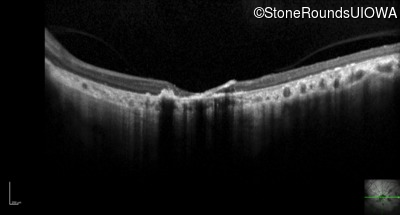

Optical Coherence Tomography - Left - 20/300 sc

Exemplar / OCT Stack

OCT Stack